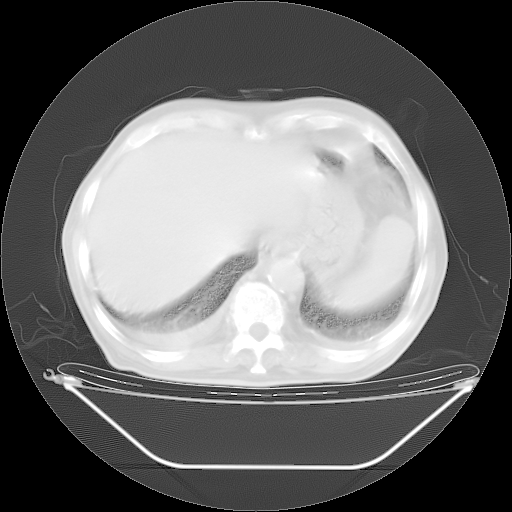

今天复查肺部CT,发现双肺广泛磨玻璃样改变。所以我把3月19日和5月9日相隔50天的肺部CT上传。请大家会诊。

2009年3月19日肺部CT片。

5月9日肺部CT(在4月27日齐鲁医院肺部CT描述部分肺组织磨玻璃样改变,12天后肺组织广泛磨玻璃样改变)